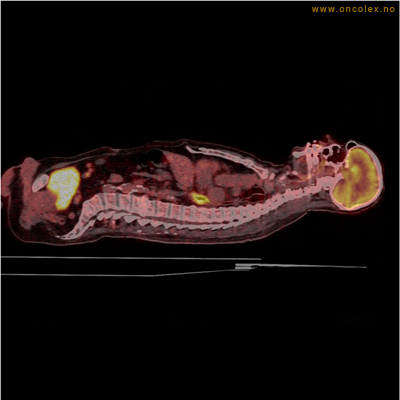

Vev som tar opp mer radioaktivt stoff, synes som hvite områder som lyser opp mer i forhold til annet vev som tar opp mindre sukker.

Kraftig opptak i svulst i lunge.

Lungekreft med spredning til lymfeknute i lungehilus.